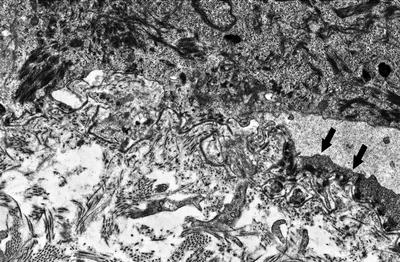

3.11.2 Histology

The blistering in epidermolysis bullosa simplex occurs within basal keratinocytes. This separation is within the cytoplasm, beneath the nuclei. Thus, the histologic appearance is that of a blister that is above the basement membrane zone, located within the basal layer of the epidermis (Fig. 3.27). In many cases, however, it is difficult to detect the small residual fragments of basal keratinocytes that remain attached to the floor of the blister, giving rise to the appearance of a subepidermal blistering process. The small fragments of basal keratinocytes tend to retract and lie flat along the basement membrane and may not be easily detected on H&E stains [92]. Ultrastructural analysis will easily resolve the level of the blistering (Fig. 3.28) [93]. Since this is a mechanically induced blistering disorder, an inflammatory infiltrate is not ordinarily part of the process, except as a secondary phenomenon that is seen in older lesions. Histologic scarring is not seen in epidermolysis bullosa simplex.

Fig. 3.28

A blister is seen above the basement membrane zone with arrows indicating keratinocyte cytoplasm at the base of the blister cavity in epidermolysis bullosa simplex (photo courtesy of Dr. John Hicks, Texas Children’s Hospital, Houston, TX)